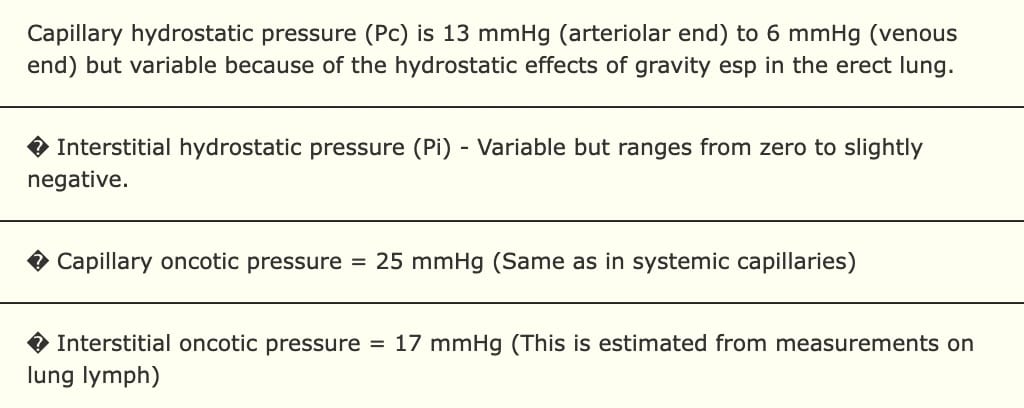

The Starling Equation in the Lung

Lung edema occurs when factors in the Starling Equation promote excessive capillary fluid filtration

We distinguish between hydrostatic and acute lung injury edema 1